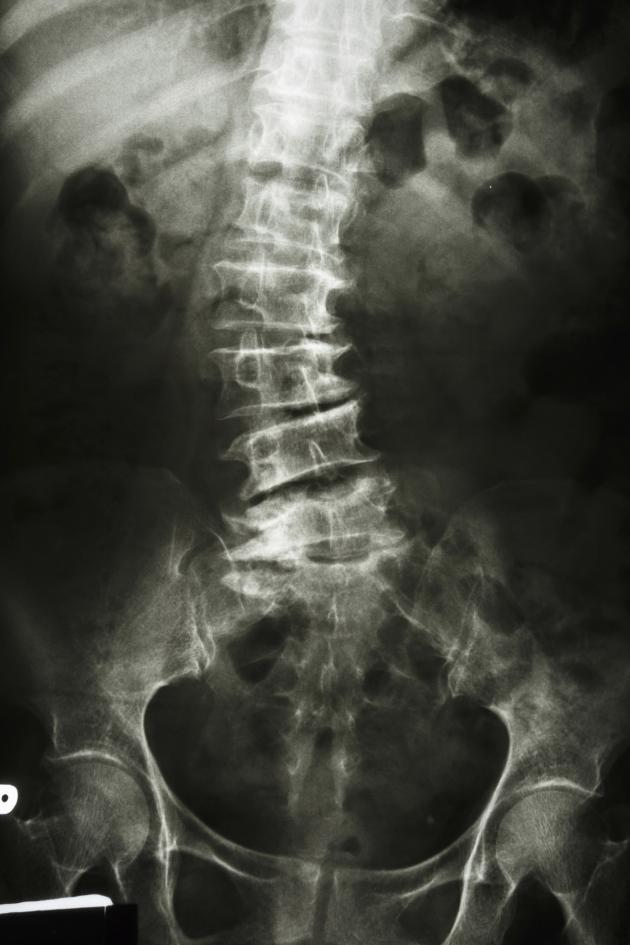

Parents can check their children’s spine to see if they have signs of scoliosis. The examination requires the child to stand erect so as to check for any curvature in the spine. Next, ask the child to bend forward with hands touching the floor and check for any curvature of the spine. If the spine looks straight, it is normal. However, parents should seek medical attention for diagnosis and follow-up so as to evaluate whether the symptoms will worsen over time if any of the following signs are observed:

- Any curvature in the spine

- Uneven shoulder levels, with one shoulder blade protruding more than the other

- Head not centred directly above pelvis

- One hip higher than the other

- Uneven rib cages

- Uneven waist creases

- Entire body leaning to one side